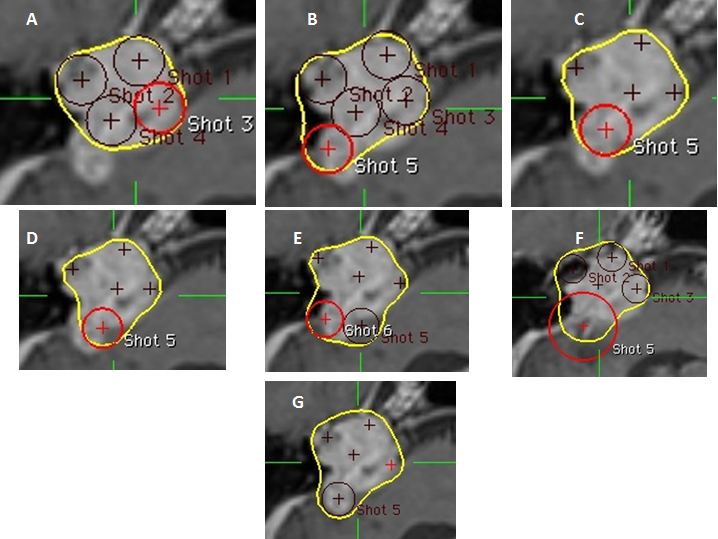

Kỹ thuật 11: Tạo hình ngón tay

Hình 10: Hình ảnh phép dựng hình ngón tay. (A) Phần tròn của khối u được bao phủ bởi đường đồng liều 50% (màu vàng). (B) Shot được đặt để bao phủ phần kéo dài hình ngón tay ở một bên. Các đường đồng liều quá rộng (C). Trọng số của shot được giảm xuống nhưng đường đồng liều “ngón tay” vẫn quá rộng ở các đoạn góc của nó. (D) Shot được dịch sang bên để giảm độ rộng của ngón tay. (E) Shot thứ hai được đặt để bao phủ đầu ngón tay. Đường đồng liều quá rộng. (F) Shot được đặt sang bên để giảm độ rộng đầu mút ngón tay. (G) Điều chỉnh nhỏ ở trọng số và vị trí của shot đầu tiên để tăng độ tương thích.

Bệnh nhân Trần Văn Th.; nam, 46 tuổi. Chẩn đoán: U dây thần kinh số VIII(P), chỉ định xạ phẫu dao gamma quay (RGK) liều 14Gy”.